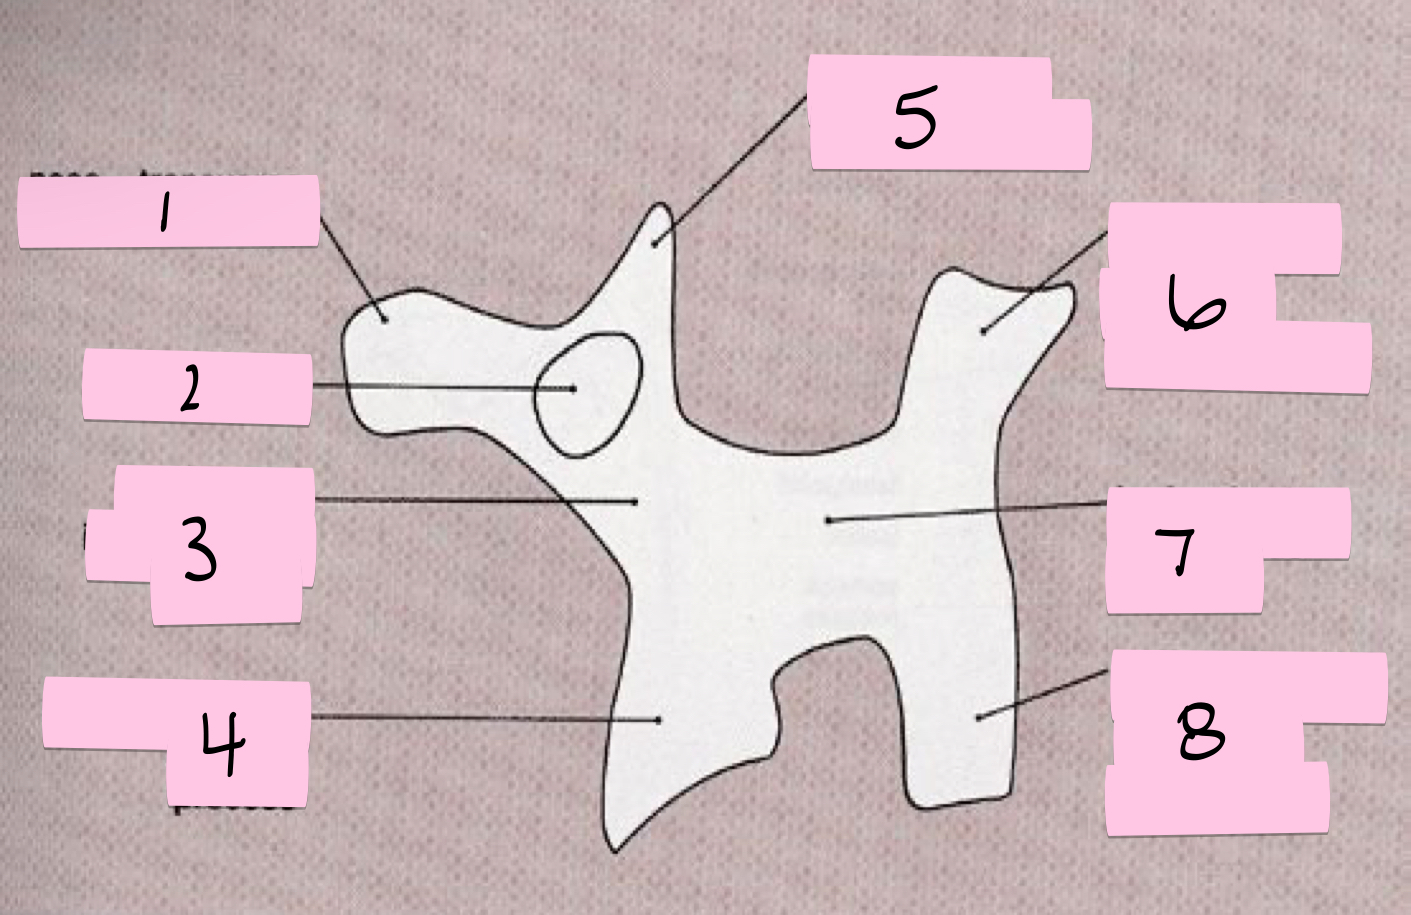

What is 1 pointing to?

Nose- Transverse process

What is 2 pointing to?

Eye- Pedicle

What is 3 pointing to?

Neck- Pars interacticularis (isthmus)

What is 4 pointing to?

Foreleg- Inferior articular process

What is 5 pointing to?

Ear- Superior articular process

What is 6 pointing to?

Tail- Superior articular process of opposite side

What is 7 pointing to?

Body- Lamina and spinous process

What is 8 pointing to?

Hindleg- Inferior articular process of opposite side